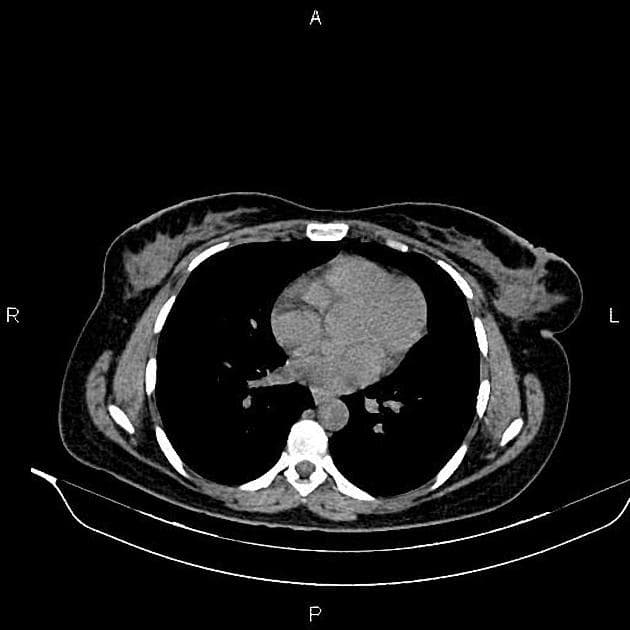

- Một khối nang khu trú một phần lồi ra ngoài (exophytic) kích thước 48 mm, thành dày ngấm thuốc (enhancement) và có các vách ngăn cùng các nốt ngấm thuốc lệch tâm (eccentric enhancing nodules) được ghi nhận ở phần giữa của thận phải.

- Một vài mạch máu tuần hoàn bàng hệ (collateral circulation) nhỏ giãn được ghi nhận trong khoảng gian thận (perinephric space).

- Ngoài ra, thấy một vài nang đơn thuần (simple cortical cysts) ở vỏ thận hai bên.

Khối nang thận - phân loại Bosniak IV (Renal cystic mass - Bosniak class IV)

- "Các khối nang thận phân loại Bosniak IV có nguy cơ ác tính từ 70-90% và thường là ung thư biểu mô tế bào thận dạng nang."

- "Các đặc điểm hình ảnh chính bao gồm thành dày ngấm thuốc, vách ngăn ngấm thuốc và các nốt ngấm thuốc lệch tâm."